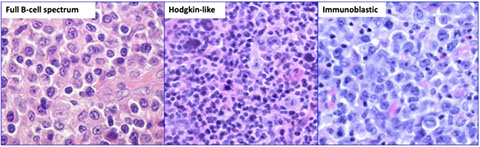

- 1/3 of pts disease free for 10 yrs, but usually progresses to MM in 2-3 years

-Adverse px factors are osteopenia and low levels of other Igs, which suggest occult myeloma

plasmacytoma of rib [14]

Solitary Plasmacytoma with Minimal BM Involvement